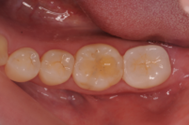

歯根破折した歯に対してRidge Preservationを行いインプラント埋入を行ったケースの症例紹介

Before

抜歯およびRidge Preservation時の口腔内写真

抜歯時に頬側の骨の大きな欠損を認めた。サイトランス®を使用したRidge Preservation、Cytoplast®※を使用し抜歯窩を被覆

(※) 未承認医薬品等であるため医薬品副作用被害救済制度の対象とはならない可能性があります。

治療中

骨の再生が起きており十分な骨幅を認める

After

補綴後の口腔内写真

主訴

他院で歯が割れていると診断され、インプラントを勧められました

治療内容

マイクロスコープにて歯の破折を確認し、患者さんとも相談の上、抜歯しインプラント埋入となった

治療費

60万円(税込)

治療期間

9ヶ月

治療回数

12回

想定されたリスク

※術後の一時的な腫れや感染のリスクがありました。

中山亮平先生

戸越なかやま歯科

破折歯を抜歯した場合、今回のケースのように骨の吸収が著しく生じていることが多く、このままではインプラント周囲に十分な骨幅(理想的にはプラットフォームから2mmの骨幅)を維持することができないためRidge Preservationは非常に有効な手法であると考える。